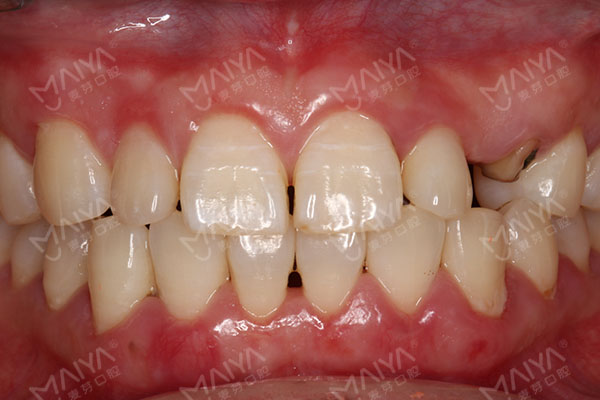

向女士牙齿情况